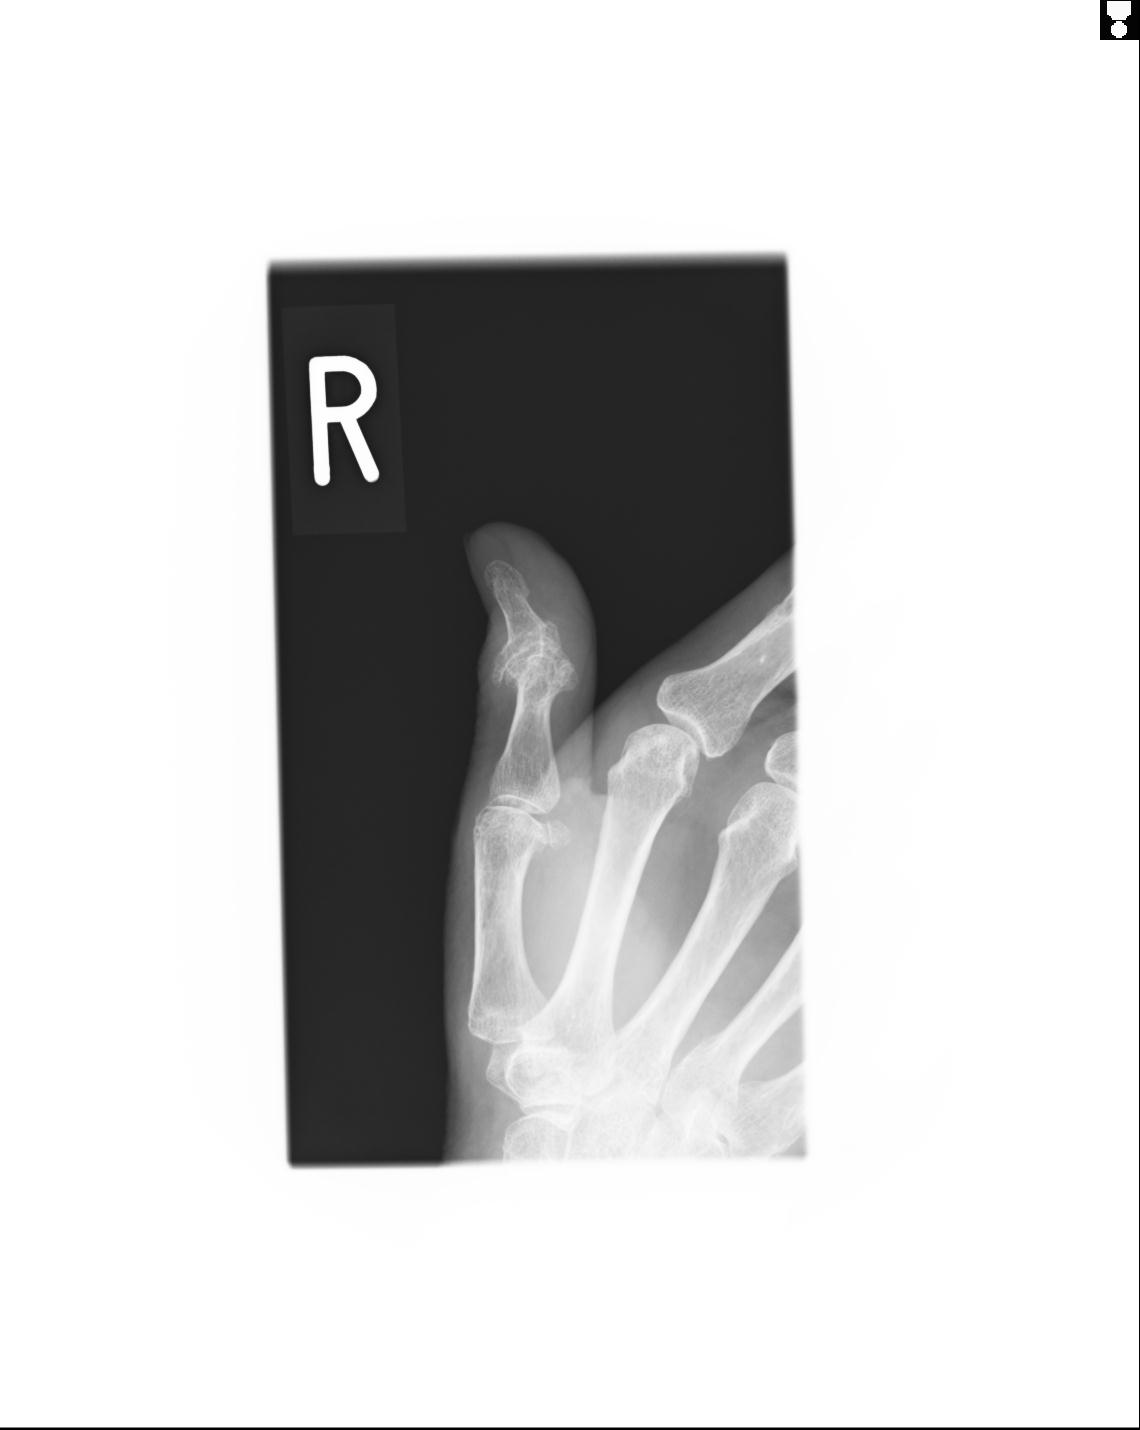

20857 1/11 左手 3R 1/19 4R 55歳男性 小指中節骨骨折